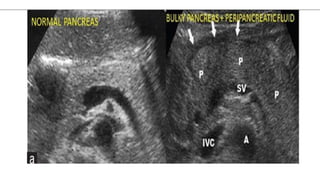

USG Abdomen Detect gallstones

Identify area of necrosis –hypoechoic regions

Transverse ultrasound demonstrates

diffuse enlargement of the pancreas ,

which appears abnormally hypoechoic